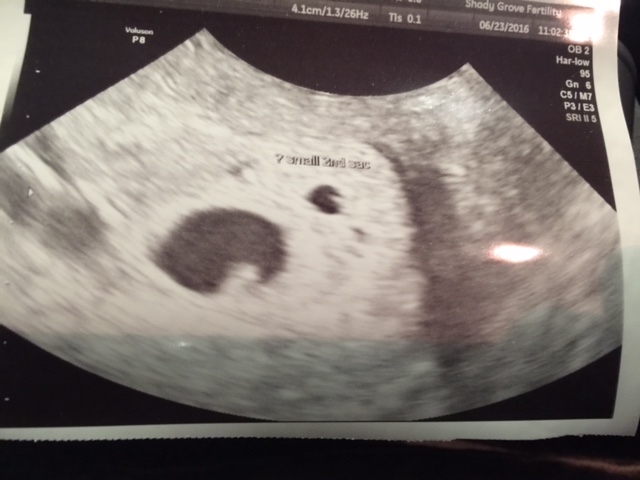

1st U/S 6/23/16 - Two babies! One measuring 6w1d with a visible heartbeat!!! The other is measuring small and isn't likely to make it